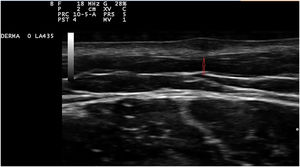

O exame dermatológico revelou a presença de pequenos nódulos elásticos com bordas mal definidas, cobertos por pele levemente hiperpigmentada e de consistência fibroelástica (fig. 1). Alguns apresentavam dor à palpação. A ultrassonografia dos nódulos no braço e na coxa esquerdos revelou lesões hipoecóicas altamente vascularizadas (fig. 2).